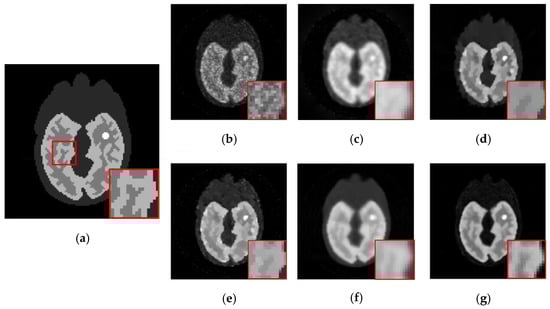

Figure 7.

The simulated low-dosed images reconstructed by different algorithms. First row: the 11th frame under 186,337 photon counts. Second row: the 11th frame under 619,848 photon counts. (a) ML-EM (12.51 dB, 15.06 dB), (b) PWLS (15.89 dB, 16.67 dB), (c) TV-AL (16.09 dB, 16.45 dB), (d) PLH-IO (16.83 dB, 18.84 dB), (e) ST-TV (17.43 dB, 19.21 dB), (f) Ours (17.78 dB, 19.98 dB).

Figure 9.

The 2nd frame of the dynamic cardiac real data, under 221,858 photon counts. The ROI is marked by a red circle. (a) ML-EM (CNR = 10.97), (b) PWLS (CNR = 13.72), (c) TV-AL(CNR = 18.46), (d) PLH-IO (CNR = 19.59), (e) ST-TV (CNR = 22.06), (f) Ours (CNR = 22.70), (g) the intensity profile across the ROI (the yellow line in the first graph). Our proposed method presents a superior contrast between the ROI and background region.

The initial experiment focuses on the resolution and the denoising performance throughout the temporal dimension. According to the TAC in Figure 4, the distinction of activity between different ROIs is inconspicuous in the early imaging stage, which consequently hampers the recovery of the structural information in the corresponding image frames. As demonstrated in Figure 6, the reconstructions of ML-EM and PWLS suffer from severe iterative noise and fail to recover a clear boundary between regions. On the other hand, the TV-AL and PLH-IO show more acceptable results for the 17th frame. However, when it comes to former frames, neither of these two methods are able to recover clear structures. Moreover, the TV-AL suffers from the staircase effect and artifacts, and PLH-IO tends to over-smooth the image. Although ST-TV improves the resolution by incorporating temporal information, it is still limited by recovering more detailed structures. In contrast, our proposed method manages to recover more detailed structures and less noise in reconstructing the brain phantom sequence under photon counts. This contrast is more distinctive in simulated low-dose images. As we can see in Figure 7, when recovering early frames in the low-count data, our proposed method is able to recover substantially clearer structures than those of other methods under similar noise levels.

Meanwhile, our method also shows its universality in recovering sequences under different sizes and TACs. In this experiment, 111 111 sized Zubal head phantom data were tested in an 18F-FDG environment. In Figure 8, the 15th frame is randomly selected out of 24 frames. In addition, real patient data are tested. In Figure 9, the second sequence is shown, and the photon counts are around 2.2 105. Obviously, our proposed method yields clearer boundaries and more conspicuous contrast between ROIs and the background.